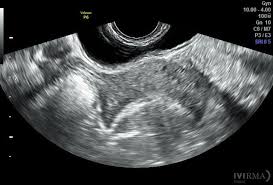

Con el desarrollo de la ecocardiografía bidimensional, se superó la limitación de las modalidades anteriores, permitiendo la visualización de imágenes en dos dimensiones de las estructuras cardíacas. Esta modalidad no solo proporciona imágenes estáticas de las cavidades y las válvulas, sino también la posibilidad de evaluar su dinámica y estructura en tiempo real desde diferentes ángulos. El uso de la ecografía bidimensional facilitó el diagnóstico de condiciones como las cardiopatías valvulares y las alteraciones en la estructura del miocardio. Este avance fue crucial para mejorar la precisión del diagnóstico y la evaluación funcional de las afecciones cardíacas.

Finalmente, el desarrollo de la ecocardiografía transesofágica (ETE) e intravascular representó un cambio significativo en la manera en que se pueden obtener imágenes del corazón y los vasos sanguíneos. La ecocardiografía transesofágica implica el uso de un transductor colocado en el esófago, lo que permite obtener imágenes de alta resolución sin la interferencia de los pulmones o la pared torácica. Esta modalidad es particularmente útil para la evaluación de estructuras cardíacas en pacientes con una anatomía difícil de evaluar con ecografía transtóracica, como en el caso de la visualización de las aurículas, las válvulas y la aorta.

La ecocardiografía intravascular, por su parte, permite la visualización detallada de las arterias coronarias a través de un catéter equipado con un transductor de ultrasonido. Esta técnica es fundamental en la valoración de enfermedades vasculares, especialmente para la detección de placas ateroscleróticas y otras condiciones que no siempre son visibles en las pruebas tradicionales.